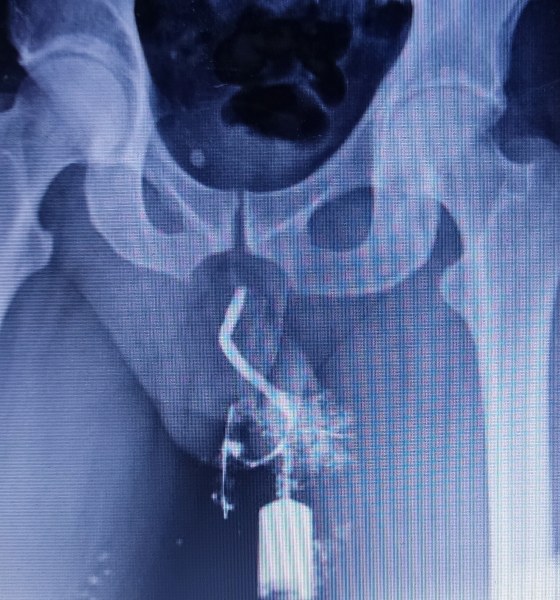

LAS FOTOS QUE ADJUNTO ACÁ ABAJO MUESTRAN TODAS LAS LESIONES QUE ME PROVOCÓ ANDRES OLIVO GARATE, UNA HERNIA INGUINEAL, ME SUTURARON EL MEATO PARA QUE SE ME CERRARA, LA LESION EN LA URETRA QUE LA HIZO YA QUE LA CIRUGIA HABIA TERMINADO PARA LUEGO QUEMARME CON EL SUPUESTO LASER, ME QUITÓ LA BASE DEL PENE Y LUEGO LE DIERON CONTINUIDAD AL DELITO CON LA CIRUGIA DEL 2022 REALIZADA EN MEDICA SUR

ME CORTÓ CON EL BISTURI OCASIONANDOME UNA LESION EN LA URETRA DE 1.6CMS, IGUALMENTE ME QUITÓ EL 70% DE LA PIEL DE MI PENE, MEDICOS PERITOS PRIVADOS NO SE PUEDEN EXPLICAR COMO SUCEDIÓ ESTO

MI ESTENOSIS ES DE 1.6 CENTIMETROS DE LARGO POR 1MM DE ANCHO CON ESPONGIOFIBROSIS ES INCREIBLE LO QUE SE PUEDE LOGRAR CON LA TELERADIOLOGIA DE PAISES DEL PRIMERO MUNDO Y LA INTELIGENCIA ARTIFICIAL. MANDÉ MIS ESTUDIOS A UN PAIS DEL PRIMER MUNDO Y ME DIERON "RESULTADOS" REALES

ESTAS FOTOS SON DE MI CUERPO LA OPERACION FUE EL 22 DE ENERO DEL 2019 , PUSIERON EN EL RECIBO UNA FECHA FALSA Y  UN NOMBRE FALSO, ELLOS SABIAN QUE HABIAN COMETIDO UNA NEGLIGENCIA MEDICA, LAS FOTOS HABLAN POR SI SOLAS, ANDRES OLIVO GARATE, ROSA ESTELA ROMERO AGUILAR Y ROMAN CARVAJAL GARCIA NO SON MEDICOS, SON CUCARACHAS QUE VIVEN Y COMEN GRACIAS A DOCTORALIA. DOCTORALIA USA HACKERS PARA HACERLE CREER A LA GENTE QUE LO QUE USTED ESTA LEYENDO EN SU PAGINA "ES REAL" TODO ES MENTIRA, O SEA LOS MEDICOS QUE NO TIENEN CLIENTES SE DAN DE ALTA EN DOCTORALIA PARA QUE ELLOS LES MANDEN CLIENTES, EN POCAS PALABRAS CUANDO USTED VEA QUE UN MEDICO EN DOCTORALIA TIENE ARRIBA DE 100 CALIFICACIONES POSITIVAS, "NO ES REAL", ES "FAKE", FALSO, CUANDO USTED VEA QUE UN MEDICO TIENE 5 A 9 COMENTARIOS EN DOCTORALIA ESE MEDICO ES "AUTENTICO" YA QUE NO SE DEJÓ EXTORSIONAR POR DOCTORALIA, DOCTORALIA AMENAZA A LOS MEDICOS QUE NO LES PAGAN CON QUEMARLOS EN REDES SOCIALES, PONEN DIRECCIONES FALSAS, EN POCAS PALABRAS DOCTORALIA SU VERDADERO NEGOCIO ES LA EXTORSION, LA MENTIRA Y LA IMPUNIDAD YA QUE TAMPOCO PAGAN IMPUESTOS EN MEXICO

AHI SE APRECIA CLARAMENTE COMO MI URETRA "GIRA" NO ESTA EN LINEA RECTA, DEBIDO A LA TENSION QUE ME PROVOCARON EN LA CIRUGIA DEL HOSPITAL MEDICA SUR EN CIUDAD DE MEXICO REALIZADA POR EL UROLOGO MARIANO OROPEZA AGUILAR

EL DOCTOR MARIANO OROPEZA Y EL DR GUILLERMO FERIA BERNAL ME PROVOCARON UN ESTRANGULAMIENTO PENO-ESCROTAL, ME QUITARON MAS DEL 50% DEL ESCROTO, HE IDO CON MUCHOS UROLOGOS QUE SOLO ME HAN DICHO MENTIRAS PARA ENCUBRIR ALGO QUE TAL VEZ NO FUE UN ACCIDENTE. GRACIAS A DIOS YA TENGO EL DICTAMEN DE PERITOS UROLOGOS QUE ESTAN EN OTRO PAIS Y SI SE PUEDE METER COMO PRUEBA DOCUMENTAL PRIVADA DEBIDO A LOS NIVELES TAN ALTOS DE CORRUPCION QUE PREVALECEN EN MEXICO

ANTES DE SER MUTILADO POR LA DOCTORA ROSA ESTELA ROMERO Y ANDRES OLIVO GARATE EN LA CIRCUNCISION DEL 2019 MI PENE ERA NORMAL, ME QUITARON EL 70% DE LA PARTE VENTRAL DEL PENE Y LUEGO EN LA SUPUESTA SEGUNDA CIRUGIA RECONSTRUCTIVA REALIZADA POR GUILLERMO FERIA BERNAL Y MARIANO OROPEZA AGUILAR EN EL HOSPITAL MEDICA SUR DE CIUDAD DE MEXICO ME QUITARON UN 50% DEL ESCROTO Y ME QUITARON LA BASE DEL PENE, FUI MUTILADO POR SEGUNDA VEZ. PARECIERA QUE AMBAS CIRUGIAS NO HAN SIDO REALIZADAS POR VERDADEROS PROFESIONALES O SI NO ES ASI ES PORQUE HA EXISTIDO DOLO O MALA FE. ME PROVOCARION "UNA DISCAPACIDAD PERMANENTE" Y VAN A ASUMIR LAS CONSECUENCIAS DE SUS ACTOS.